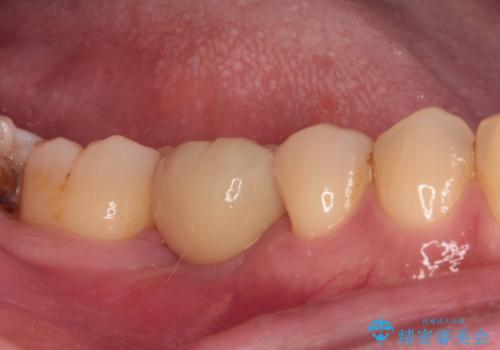

平日の昼間でもご来院可能とのことであったので、必要最小限の期間で治療を終えることができました。